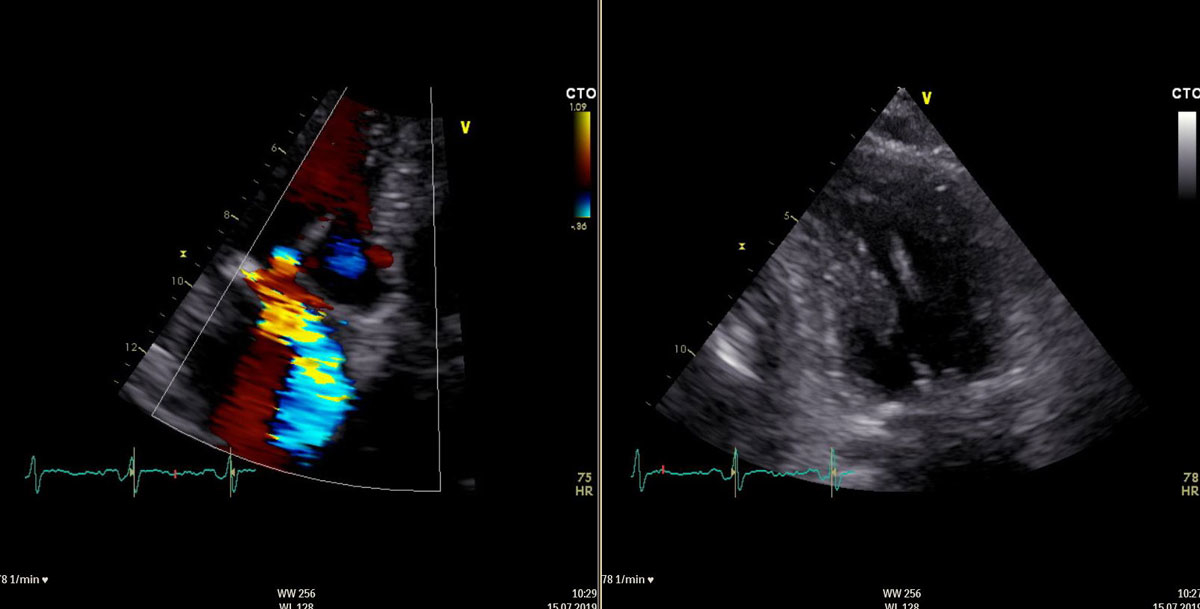

The procedure was performed through a left anterolateral thoracotomy with a 4 cm incision on the fifth intercostal space under the left breast. After preparation of the subcutaneous tissue and incision of the left pleura and the pericardium, felt-supported, purse string sutures were placed on the apex of the left ventricle (fig. 2). The apex of the left ventricle was then punctured and a guidewire placed through the aortic valve in the ascending aorta, under echocardiographic guidance. The sheath and the TAVI delivery system were introduced over the guidewire and positioned on the level of the aortic valve annulus. A 23-mm Edwards Sapien 3 valve (Edwards, Irvine, CA) was then implanted under rapid pacing with the subsequent intraoperative echocardiographic examination showing minimal paravalvular regurgitation. Afterwards, the TAVI deliver system was removed and the NeoChord system introduced (fig. 3). Subsequently, three neochords were implanted in the P2 segment under echocardiographic examination and the initially severe mitral valve regurgitation was decreased to a moderate one (fig. 4).

Figure 4 Moderate mitral valve regurgitation and implanted neochords. Postoperative transoesophageal echocardiography.